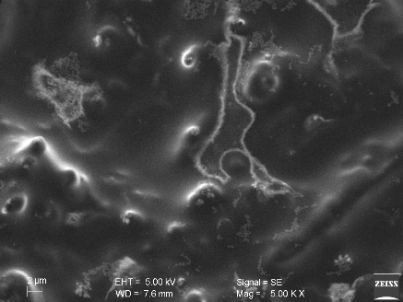

By scanning electron microscope (SEM)

Surface morphological properties of formula F2 nano size vesicles were obtained by SEM at three magnifications (1.00 K X, 5.00 K X, 10.00 K X) and shown in fig. 11. The vesicular properties of these drug carriers form double layers. SEM revealed the morphology of the vesicles and the arrangement of the lamellar structure encapsulating the drug molecules [34].

(A) (B) (C)

Fig. 11: Scanning electron micrographs of proniosomal formula F2 at three different magnification powers (A)1.00 K X, (B)5.00 K X, (C)10.00 K X)